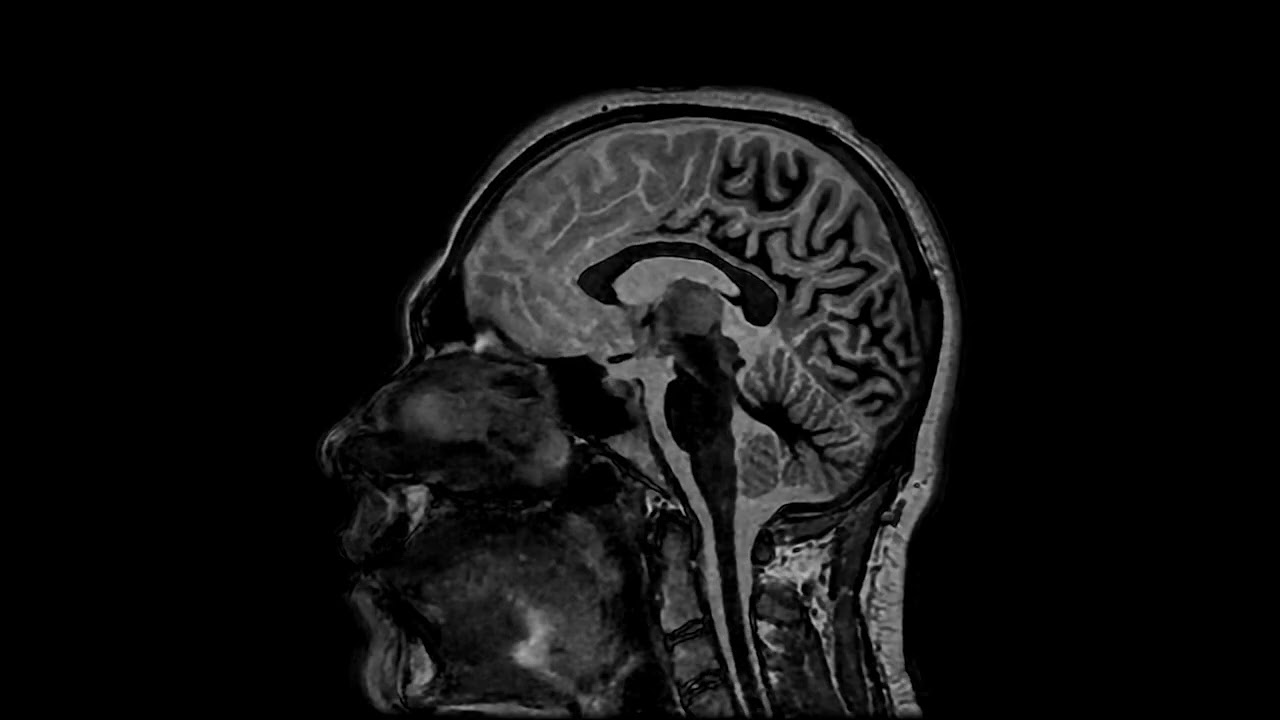

💢3D Axial BRAVO White Matter Nulling with HyperSense & AIR Recon DL

• Voxel Size: 1x 1 x 1.mm

• Scan time: 4:39

✳️By employing a TI for white matter nulling, we significantly enhanced the contrast between the basal ganglia and surrounding tissues.